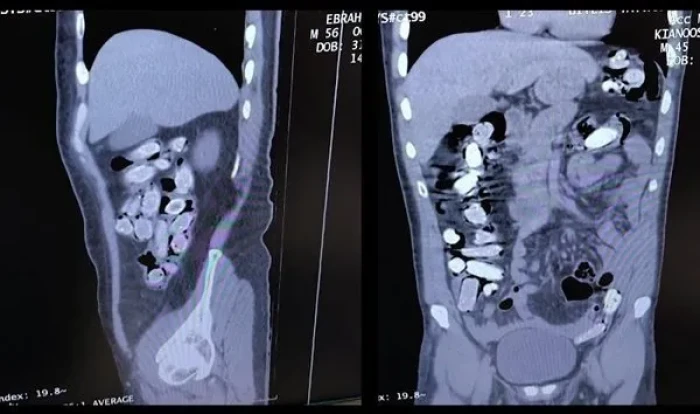

Bitlis Tatvan Devlet Hastanesine götürülen şüphelilerin röntgen ve tomografilerinde, mide ve bağırsaklarında çok sayıda yabancı cisim olduğu belirlendi.

Şüphelilerin yuttuğu 136 kapsüldeki 1 kilo 48 gram sentetik uyuşturucu, tıbbi müdahaleyle mide ve bağırsaklardan çıkarıldı.